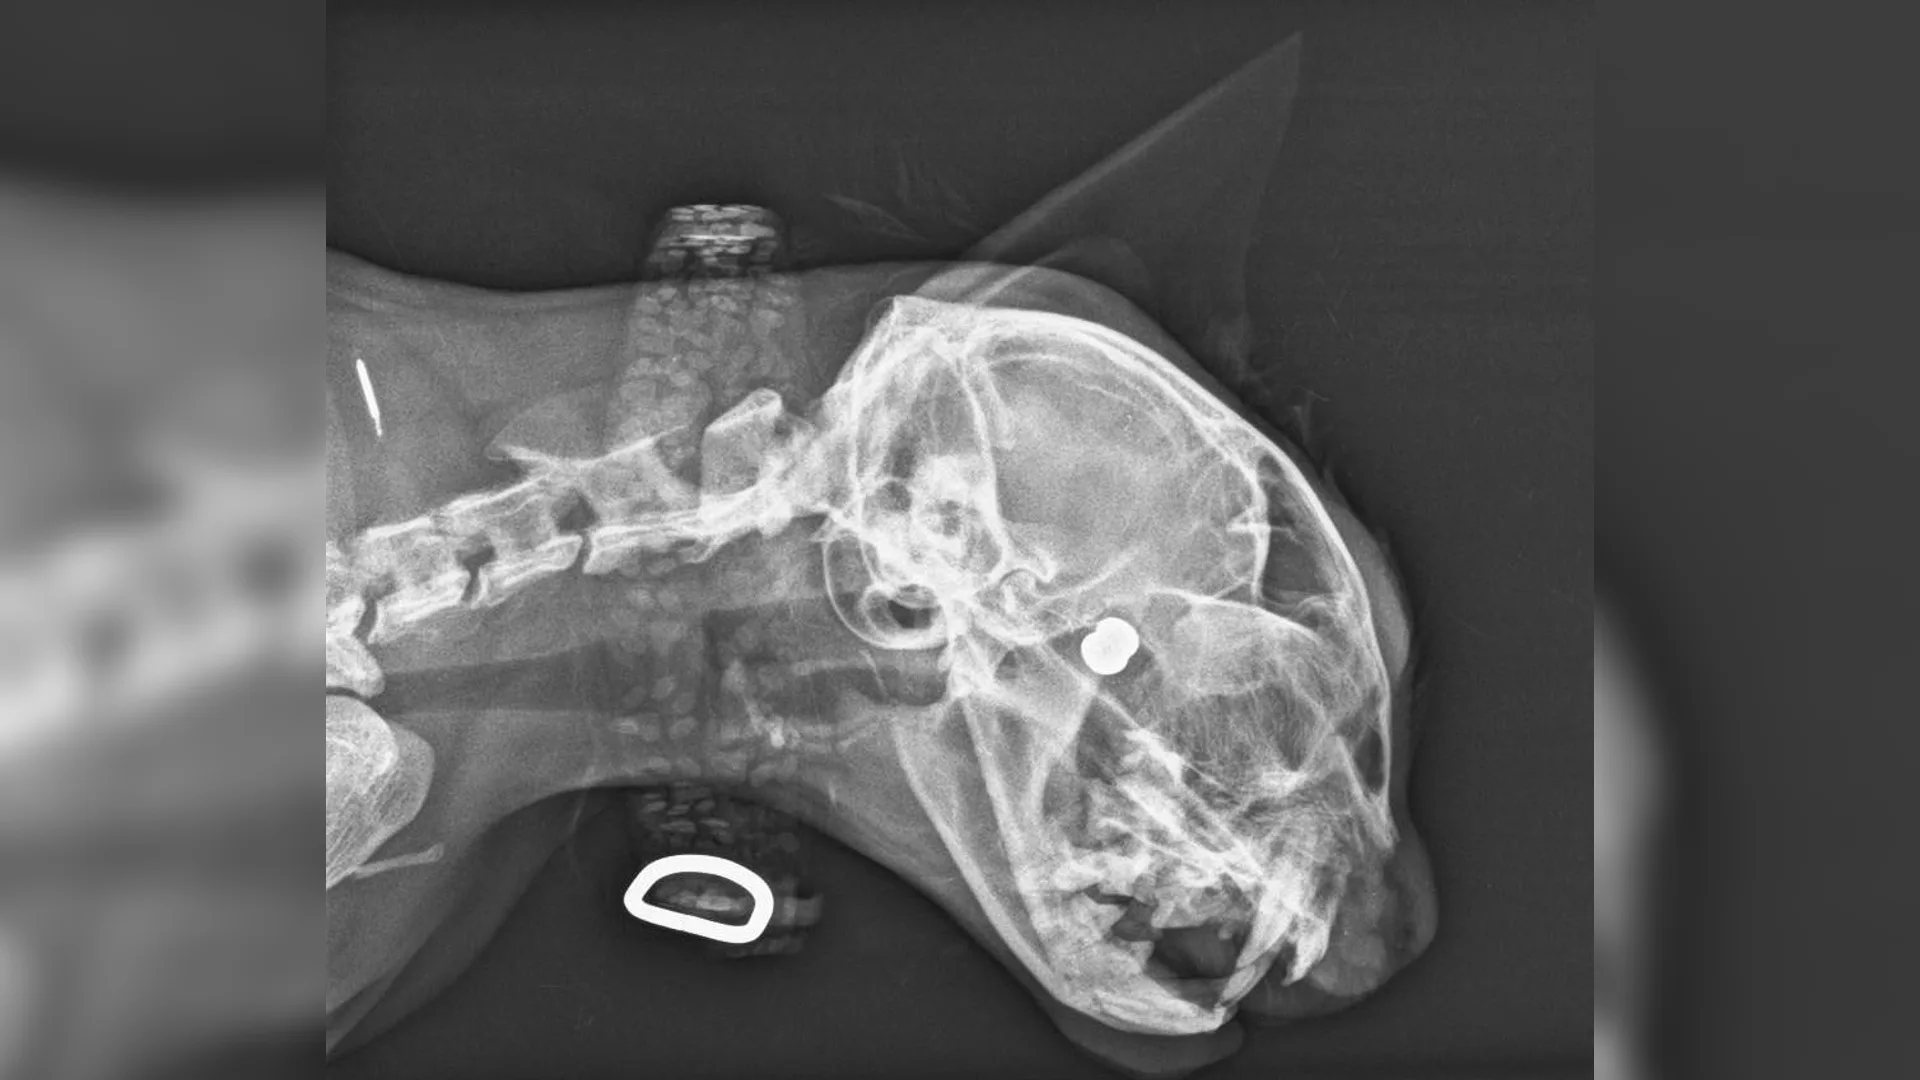

"Medewerkers van de gemeente zagen hem half verlamd in de greppel liggen. Toen is hij naar de dierenarts gebracht. Die heeft een scan gemaakt en daaruit bleek dat hij een kogel in z'n rug had", zegt Roselie. "Dat was een erge schok. Hij kroop maar een beetje rond in de kooi."

Uiteindelijk is Bo naar een specialist gebracht die hem zou kunnen opereren. "De dokter had hem toen onderzocht. Het bleek dat hij niet meer zelfstandig kon poepen en plassen. Daarnaast zou hij misschien botsplinters hebben, maar daarvoor moest een CT-scan worden gemaakt." Helaas was Bo daar te zwak voor, omdat bleek dat hij een dwarslaesie had.